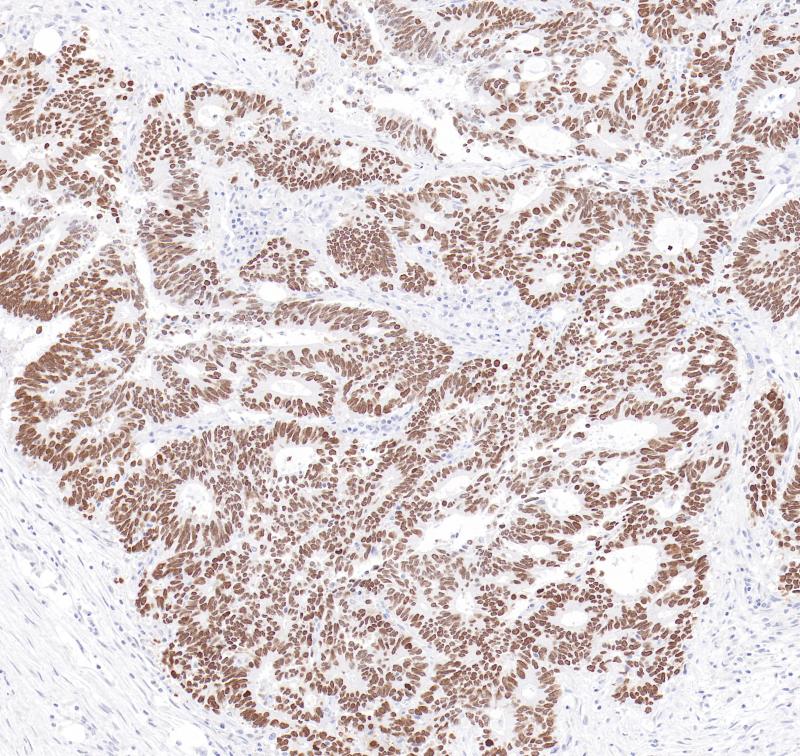

GCDFP-15即gross cystic disease fluid protein 15,是泌乳素诱导蛋白家族中的一员。GCDFP-15抗原可表达于非肿瘤性浆液性涎腺腺体、精囊和乳腺以及乳腺囊肿液等中,可作为乳腺癌标记物。该抗体主要用于乳腺癌的诊断,也常与mammaglobin 联用以判断乳腺癌微小病灶的转移情况。

阳性对照

乳腺癌